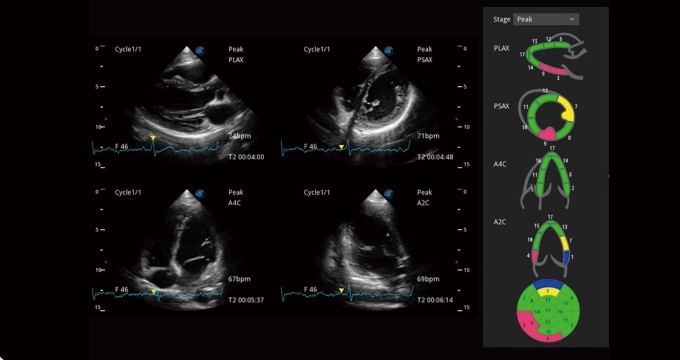

心血管应用

支持运动和药物负荷协议、多心动周期存储选择,为临床观察心肌负荷状态下的室壁节段运动、评估心肌缺血状态提供更多的解决方案。

通过心肌识别技术和二维斑点追踪技术相结合,计算心肌各节段的应变应变率、速度、位移并以曲线图显示,实现整体或者局部心肌定量分析。同时可呈现牛眼图直观和准确诊断心肌的运动情况。